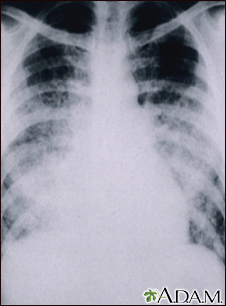

This chest x-ray shows cloudiness throughout the lungs, caused by acute pneumonia following chickenpox. Pneumonia, as a complication of chickenpox, rarely occurs in children, but is more frequent in adults.